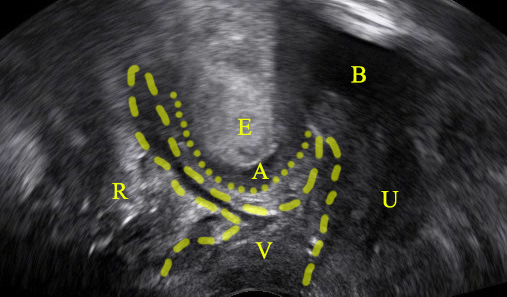

An enterocele refers to the caudal displacement of small bowel loops. Τhe enterocele typically appears in the posterior vaginal wall, but not exclusively. Rarely it might also appear in the anterior vaginal wall. In post-hysterectomy patients the enterocele sac descends through the middle, displacing the vaginal cuff caudally. Differentiating the enterocele from a rectocele and other types of prolapse is essential for proper surgical planning.

- Demonstrating peristalsis can be held as pathognomonic for small bowel loops.

- The presence of any intraperitoneal fluid may help outline the apex of the enterocele.

- Small bowel contents (ground-glass echogenicity) are usually not difficult to distinguish from stool in the rectal ampulla.

Depicting an enterocele in pelvic floor ultrasound is feasible: